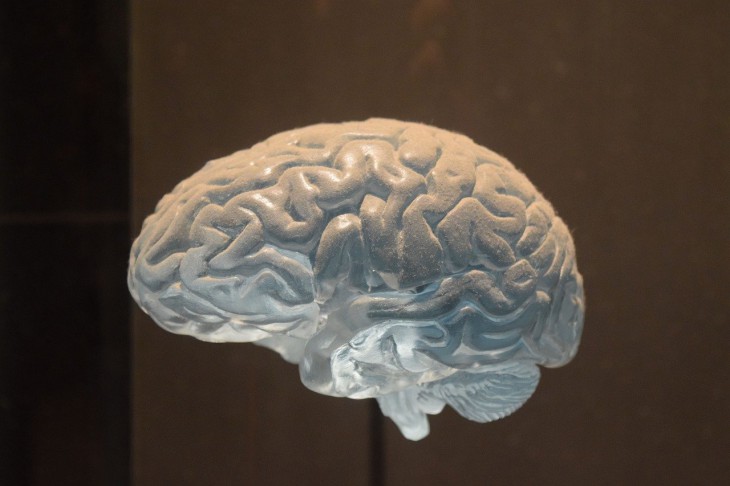

Есть предположения, что плотность ионных каналов в нейронах была уменьшена человеческим мозгом для того, чтобы сэкономить на них энергию.

Известно, что электрический импульс создается при помощи ионных каналов, являющихся белком, находящимся в клеточной мембране. Об этом пишет Nature.

У нейронов разные размеры, а также длина и ветвистость отростков. Они необходимы для того, чтобы передавать или принимать импульсы. Кроме того, у нейрона побольше ионных каналов будет побольше, чем у небольшого.